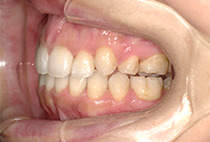

出っ歯と前歯のガタつきにお悩みだった20代女性の症例です。

金属アレルギーがあるため、メタルフリーで治療できる【インビザライン】による抜歯矯正を選択されました。

矯正治療2年6ヶ月

30回

インビザライン、インプラントアンカー、美容治療

矯正:1,137,400円+毎月調整量:6,050円